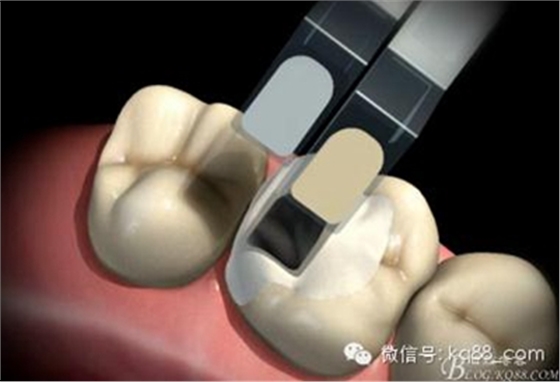

嵌體、高嵌體牙體預(yù)備相對簡單,避免倒凹即可

由于邊緣在齦上取印模容易,印模更清晰、更準(zhǔn)確